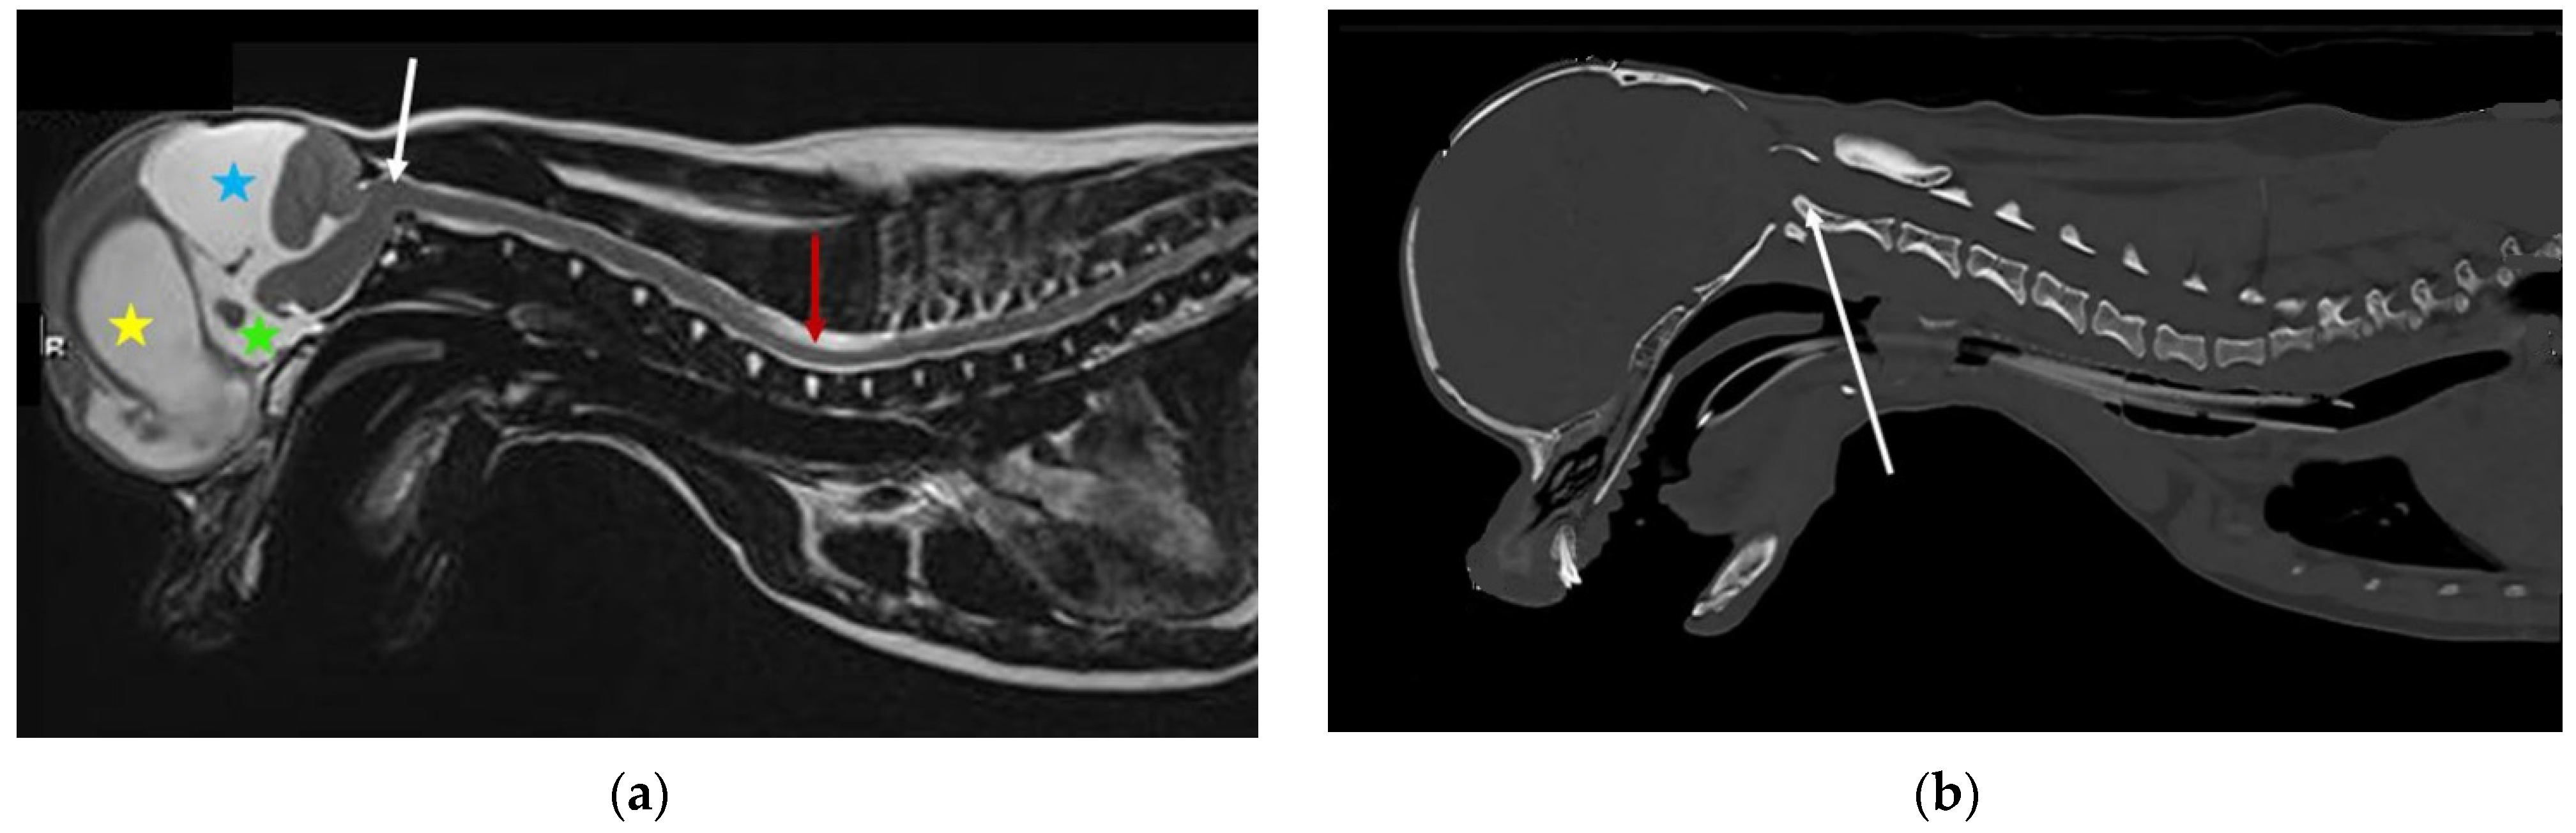

Figure 4. MRI and CT of a two-year-old female Chihuahua with hydrocephalus, quadrigeminal cistern expansion, and syringomyelia. (a) T2-weighted midsagittal brain and cervicothoracic spine. Yellow star, dilated lateral ventricle; green star, dilated third ventricle; blue star, quadrigeminal cistern expansion with compression of the cerebellum, which is herniated into the spinal canal. White arrow, craniocervical junction abnormality with cervical flexure, angulation of the odontoid peg, and compression of the craniospinal junction. Red arrow, developing cervicothoracic syrinx. (b) Mid-sagittal reformatted CT of the skull and cranial cervical spine. White arrow, craniocervical junction abnormality with cervical flexure, angulation of the odontoid peg, and compression of the craniospinal junction (images created by C. Rusbridge and S.P. Knowler).